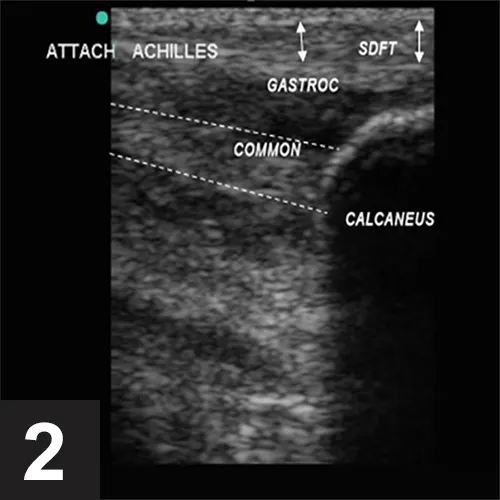

Diagnostic ultrasound revealed loss of normal architecture and echogenicity in the distal 3 cm of the tendons that make up the Achilles complex, with multiple small hypoechoic areas in the common calcaneal and gastrocnemius branches (Figure 2). The superficial digital flexor tendon (SDFT) appeared normal; however, edema could be seen within the subcutaneous tissues over the tendon. Fibers of each part of the Achilles complex could be followed to the calcaneal attachment and appeared intact, but the fiber was in a disorganized pattern (ie, loss of normal striations) and swollen. Based on ultrasound appearance, the diagnosis was consistent with a grade II/IV strain (ie, no core lesion, no full tear) of both the common calcaneal and gastrocnemius tendons.

Figure 2. Ultrasound of the Achilles complex showing loss of echogenicity in the distal gastrocnemius (gastroc) and common calcaneal tendons (common) as they attach to the calcaneus. The white lines demarcate the approximate region of the common calcaneal tendon where minimal echogenicity is seen. The superficial digital flexor tendon (SDFT) has normal echogenicity.